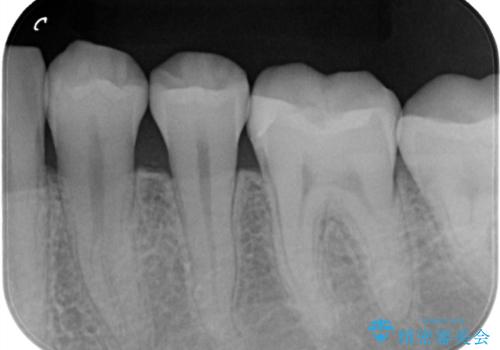

- 下の奥歯が黒いことが気になり来院された患者様です。

レントゲンなどから隣接面にも、う蝕があることが判明しました。